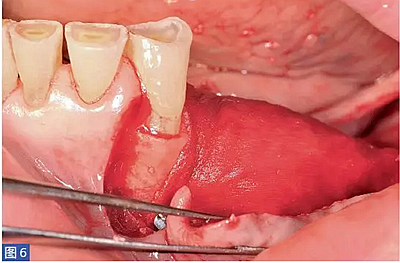

圖6:(左側(cè))病例1. 用鈦釘固定膜。

膠原可吸收膜(Bio-Gide, Geistlich)通過(guò)內(nèi)固定鈦釘固定在該區(qū)域的舌側(cè)(膜的每個(gè)角上固定一個(gè)鈦釘)。將膜反折到前庭側(cè)后,用兩個(gè)鈦釘將膜固定在頰側(cè)。所使用的膜的大小嚴(yán)格取決于無(wú)牙頜區(qū)域的近遠(yuǎn)中距離。